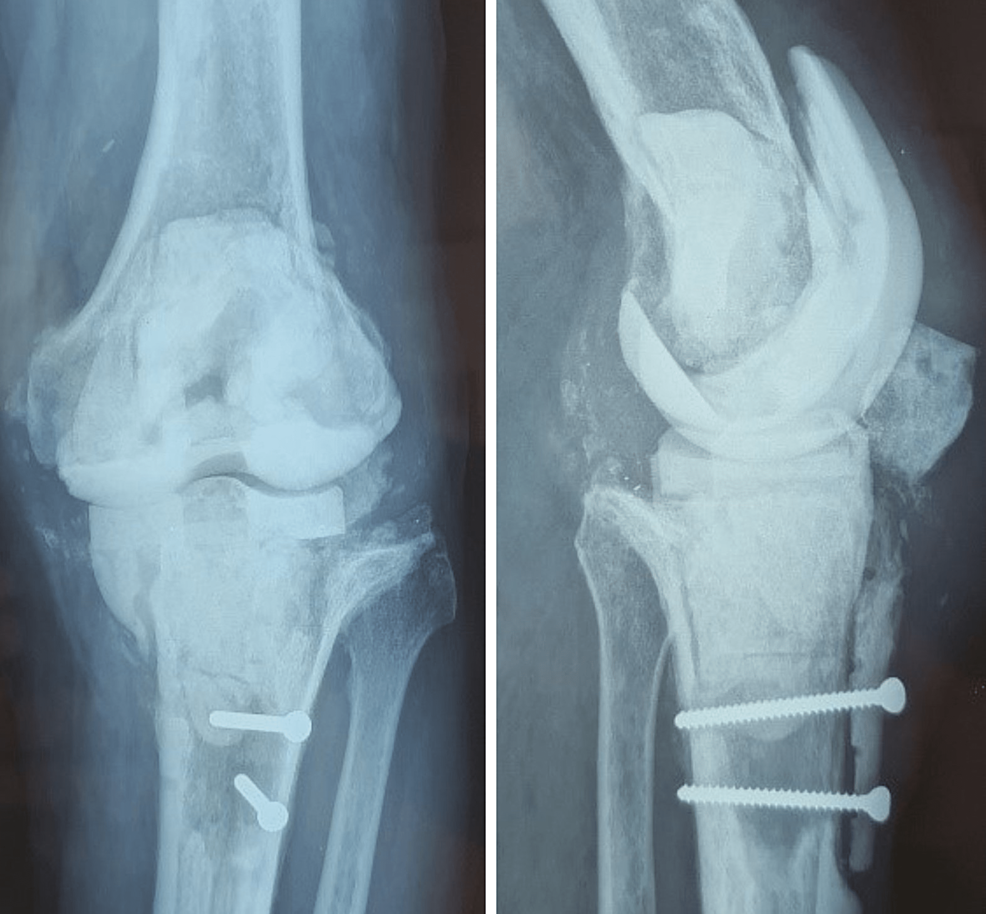

From www.laudclinic.com

Infected old Knee Replacement 2 stage Revision Knee Replacement Post Knee Replacement Infection Knee replacement infections are usually separated into categories of early versus late infections. In these cases, bacteria can adhere to. A knee replacement infection may develop after a person has had an operation to replace their knee joint. Prosthetic joint infections are serious complications of hip and knee arthroplasty and a common cause for revision arthroplasty. Great care is taken. Post Knee Replacement Infection.